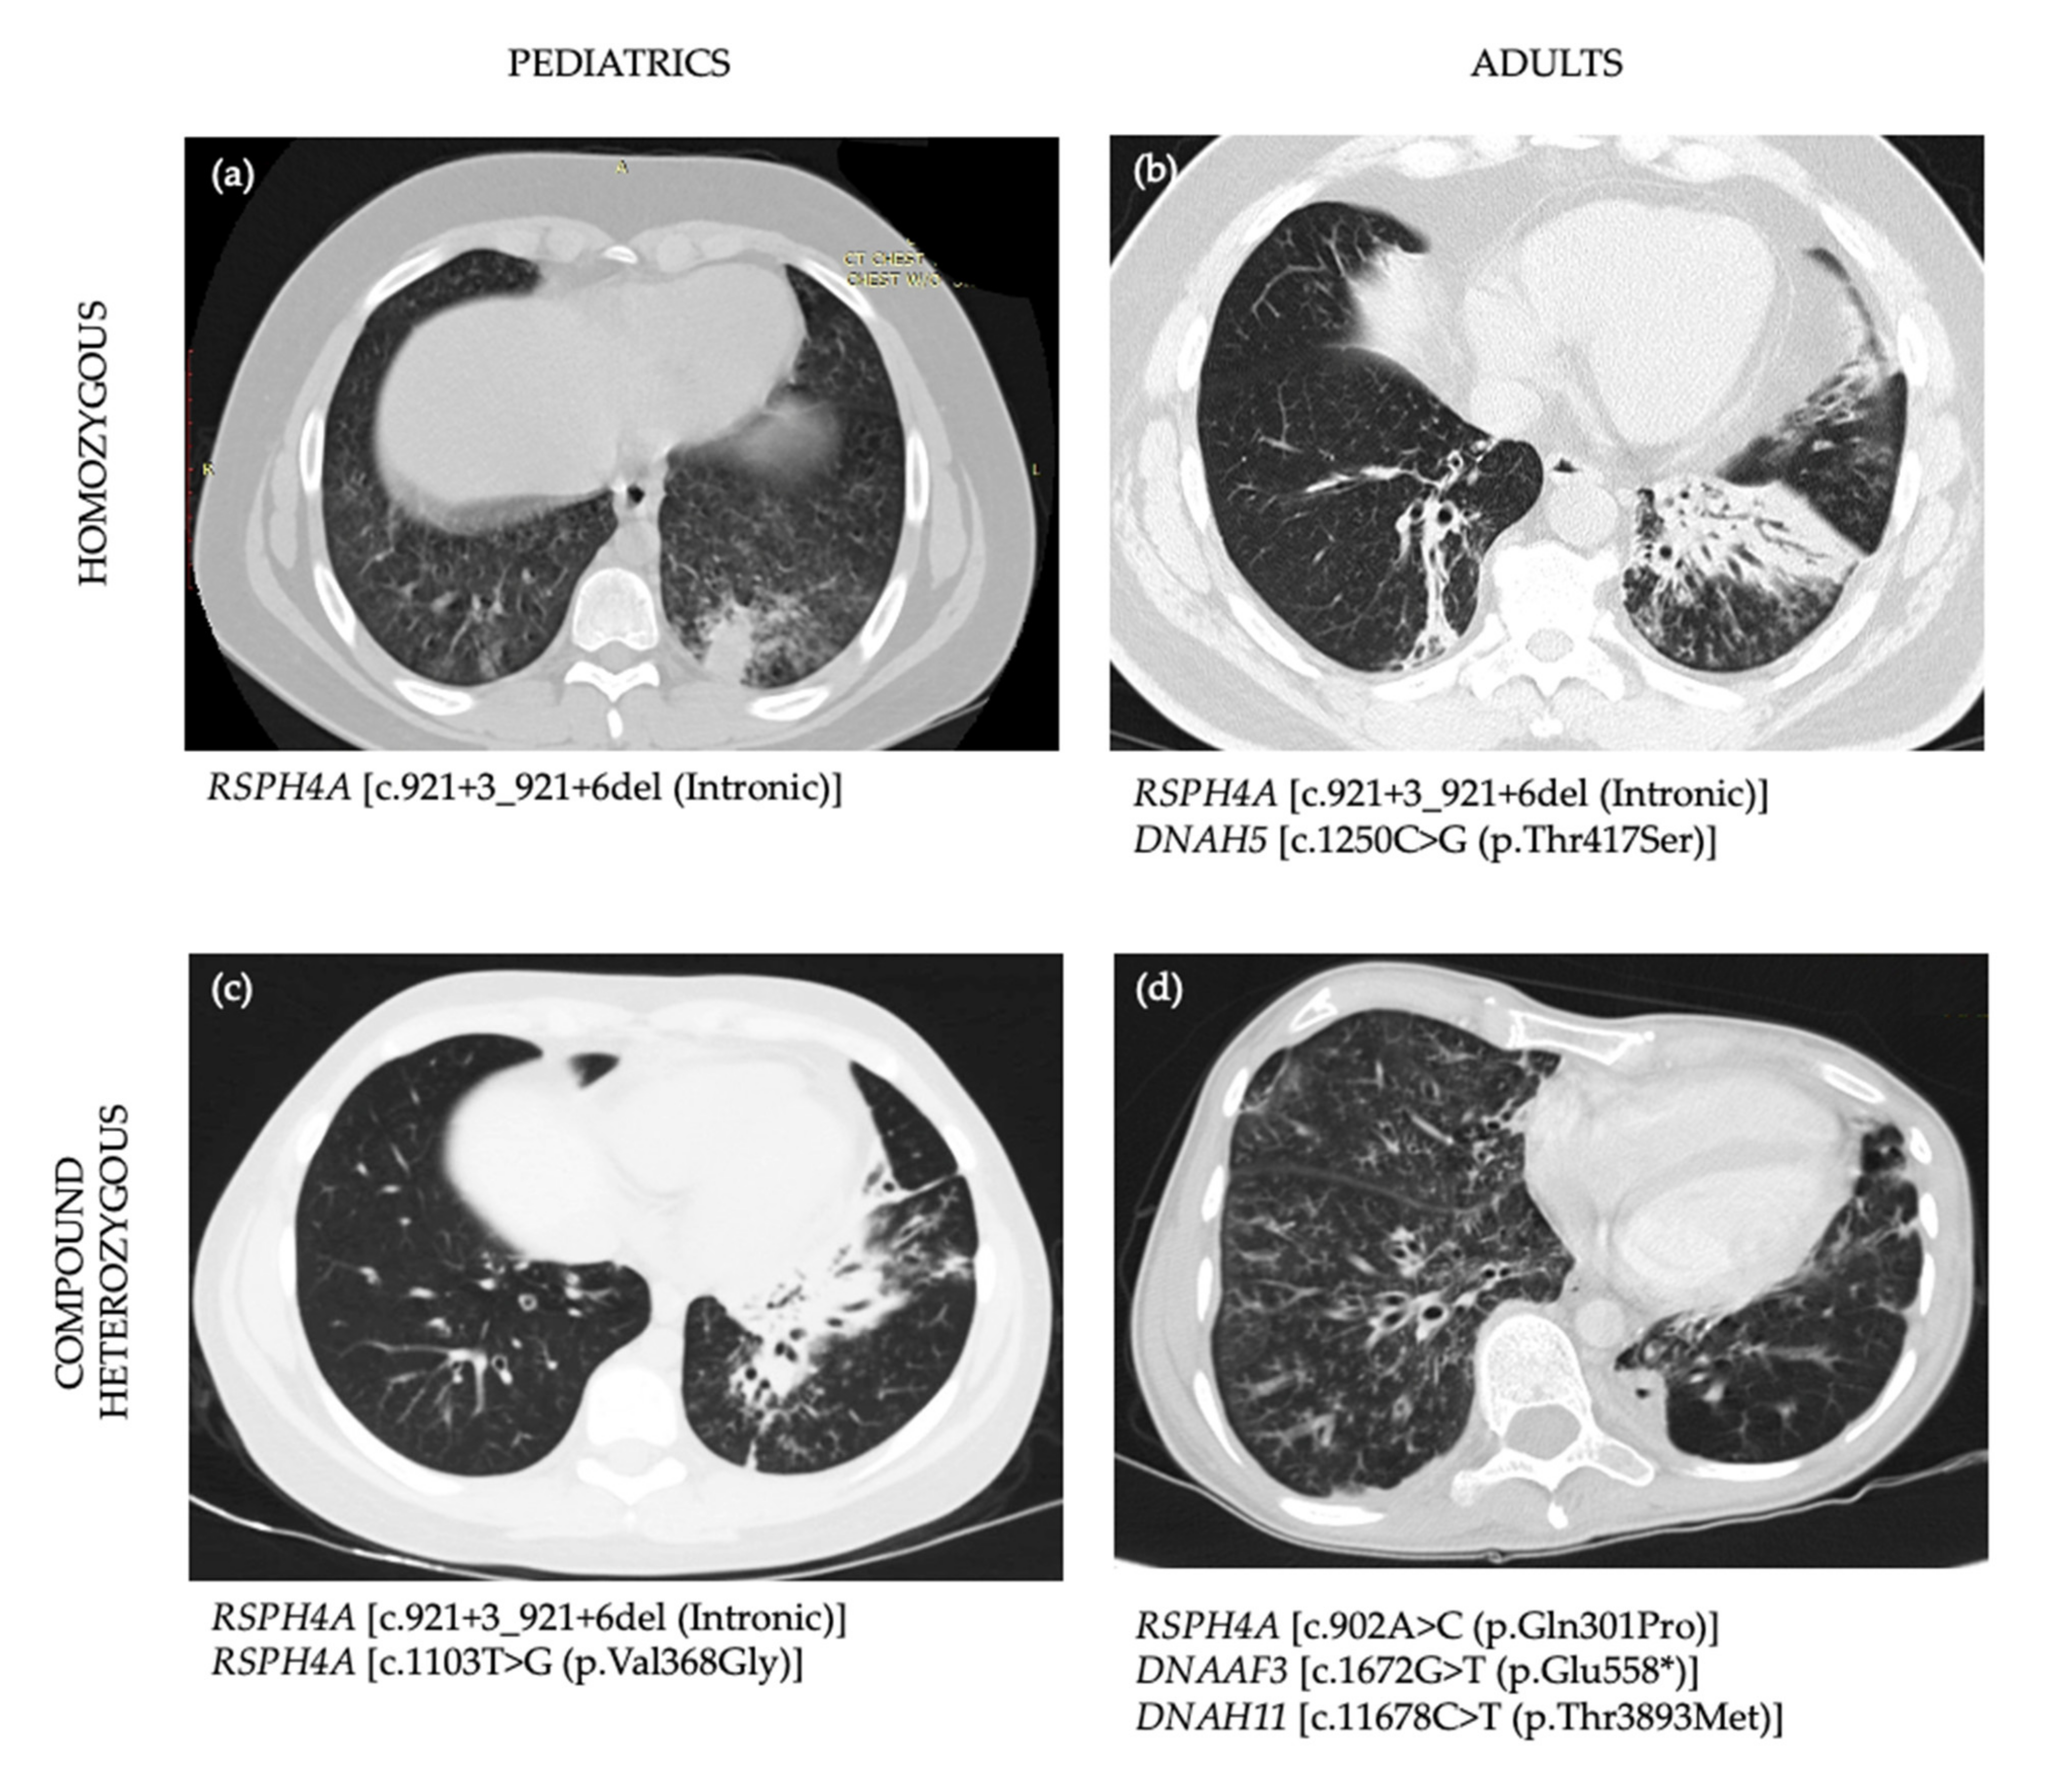

3.4. Imaging